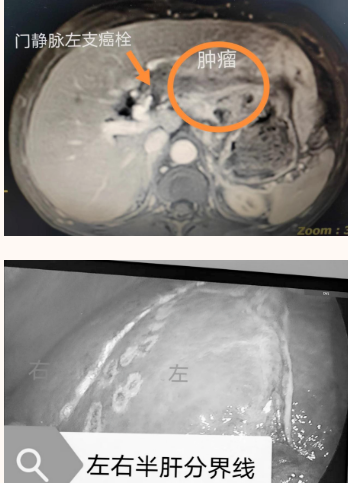

该患者既往有慢性乙型病毒性肝炎、乙型肝炎后肝硬化病史,上中腹部核磁共振(MRI)检查并结合病史及其他辅助检查,考虑肝左叶原发性肝癌,门静脉左支癌栓。在徐耀端主任的带领下,经过全科团队讨论研究,为患者制定了“腹腔镜下解剖性左半肝切除术”的治疗方案。尽管该手术技术难度较大,在州内腹腔镜下暂未开展,但在徐耀端主任、孙春权主治医师的严密配合、精诚合作下,最终顺利完成手术,术后患者恢复迅速且良好,消除了病痛的折磨。